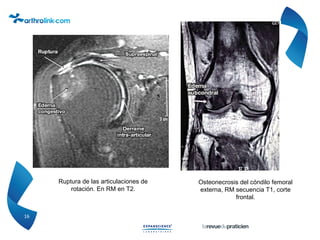

Corte frontal FSE T2 Artrosis FT lesión

interna cartilaginosa meseta y cóndilo

de grado 4, edema de la meseta tibial y

del cóndilo.

Gonartrosis edema tibial e

inflamación sinovial. Cortes

sagitales FSE T2.